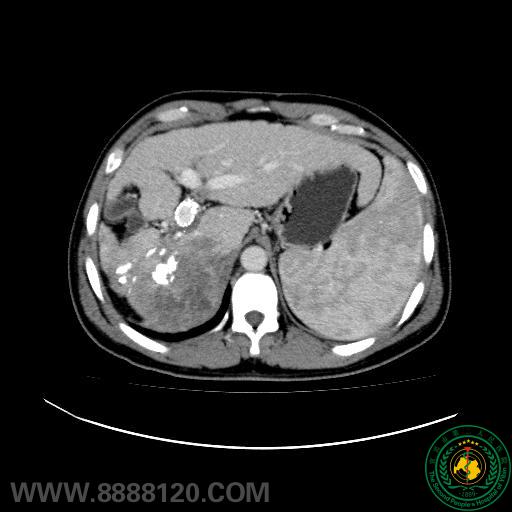

影像科介入室肝癌介入治疗取得新进展

影像科介入室肝癌介入治疗取得新进展2919